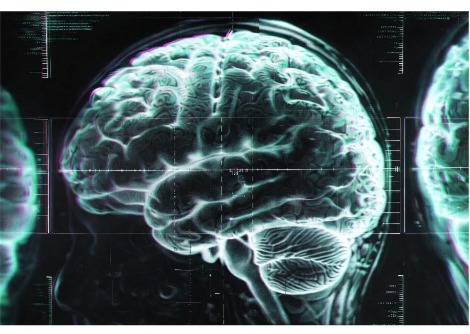

تتأثر آلام أسفل الظهر بالعديد من العوامل ، بما في ذلك البيولوجية والاجتماعية والنفسية . يعني التعقيد التشريحي للعمود الفقري البشري أنه في معظم الحالات ، لا يمكن تحديد سبب بنيوي بسيط مثل مفصل أو عضلة واحدة ، حتى مع التصوير التشخيصي المتطور.

هذا يعني أن التشخيص يتم إلى حد كبير على أساس الأعراض المبلغ عنها  . وعلى الرغم من أن معظم حالات آلام أسفل الظهر قصيرة الأجل ، مع التعافي خلال الأسابيع الستة الأولى من ظهور الألم ، فإن ثلث الحالات ستصبح مستمرة وقد تستمر لسنوات. استمرار الألم يساهم  في العبء الكبير لهذه الحالة .